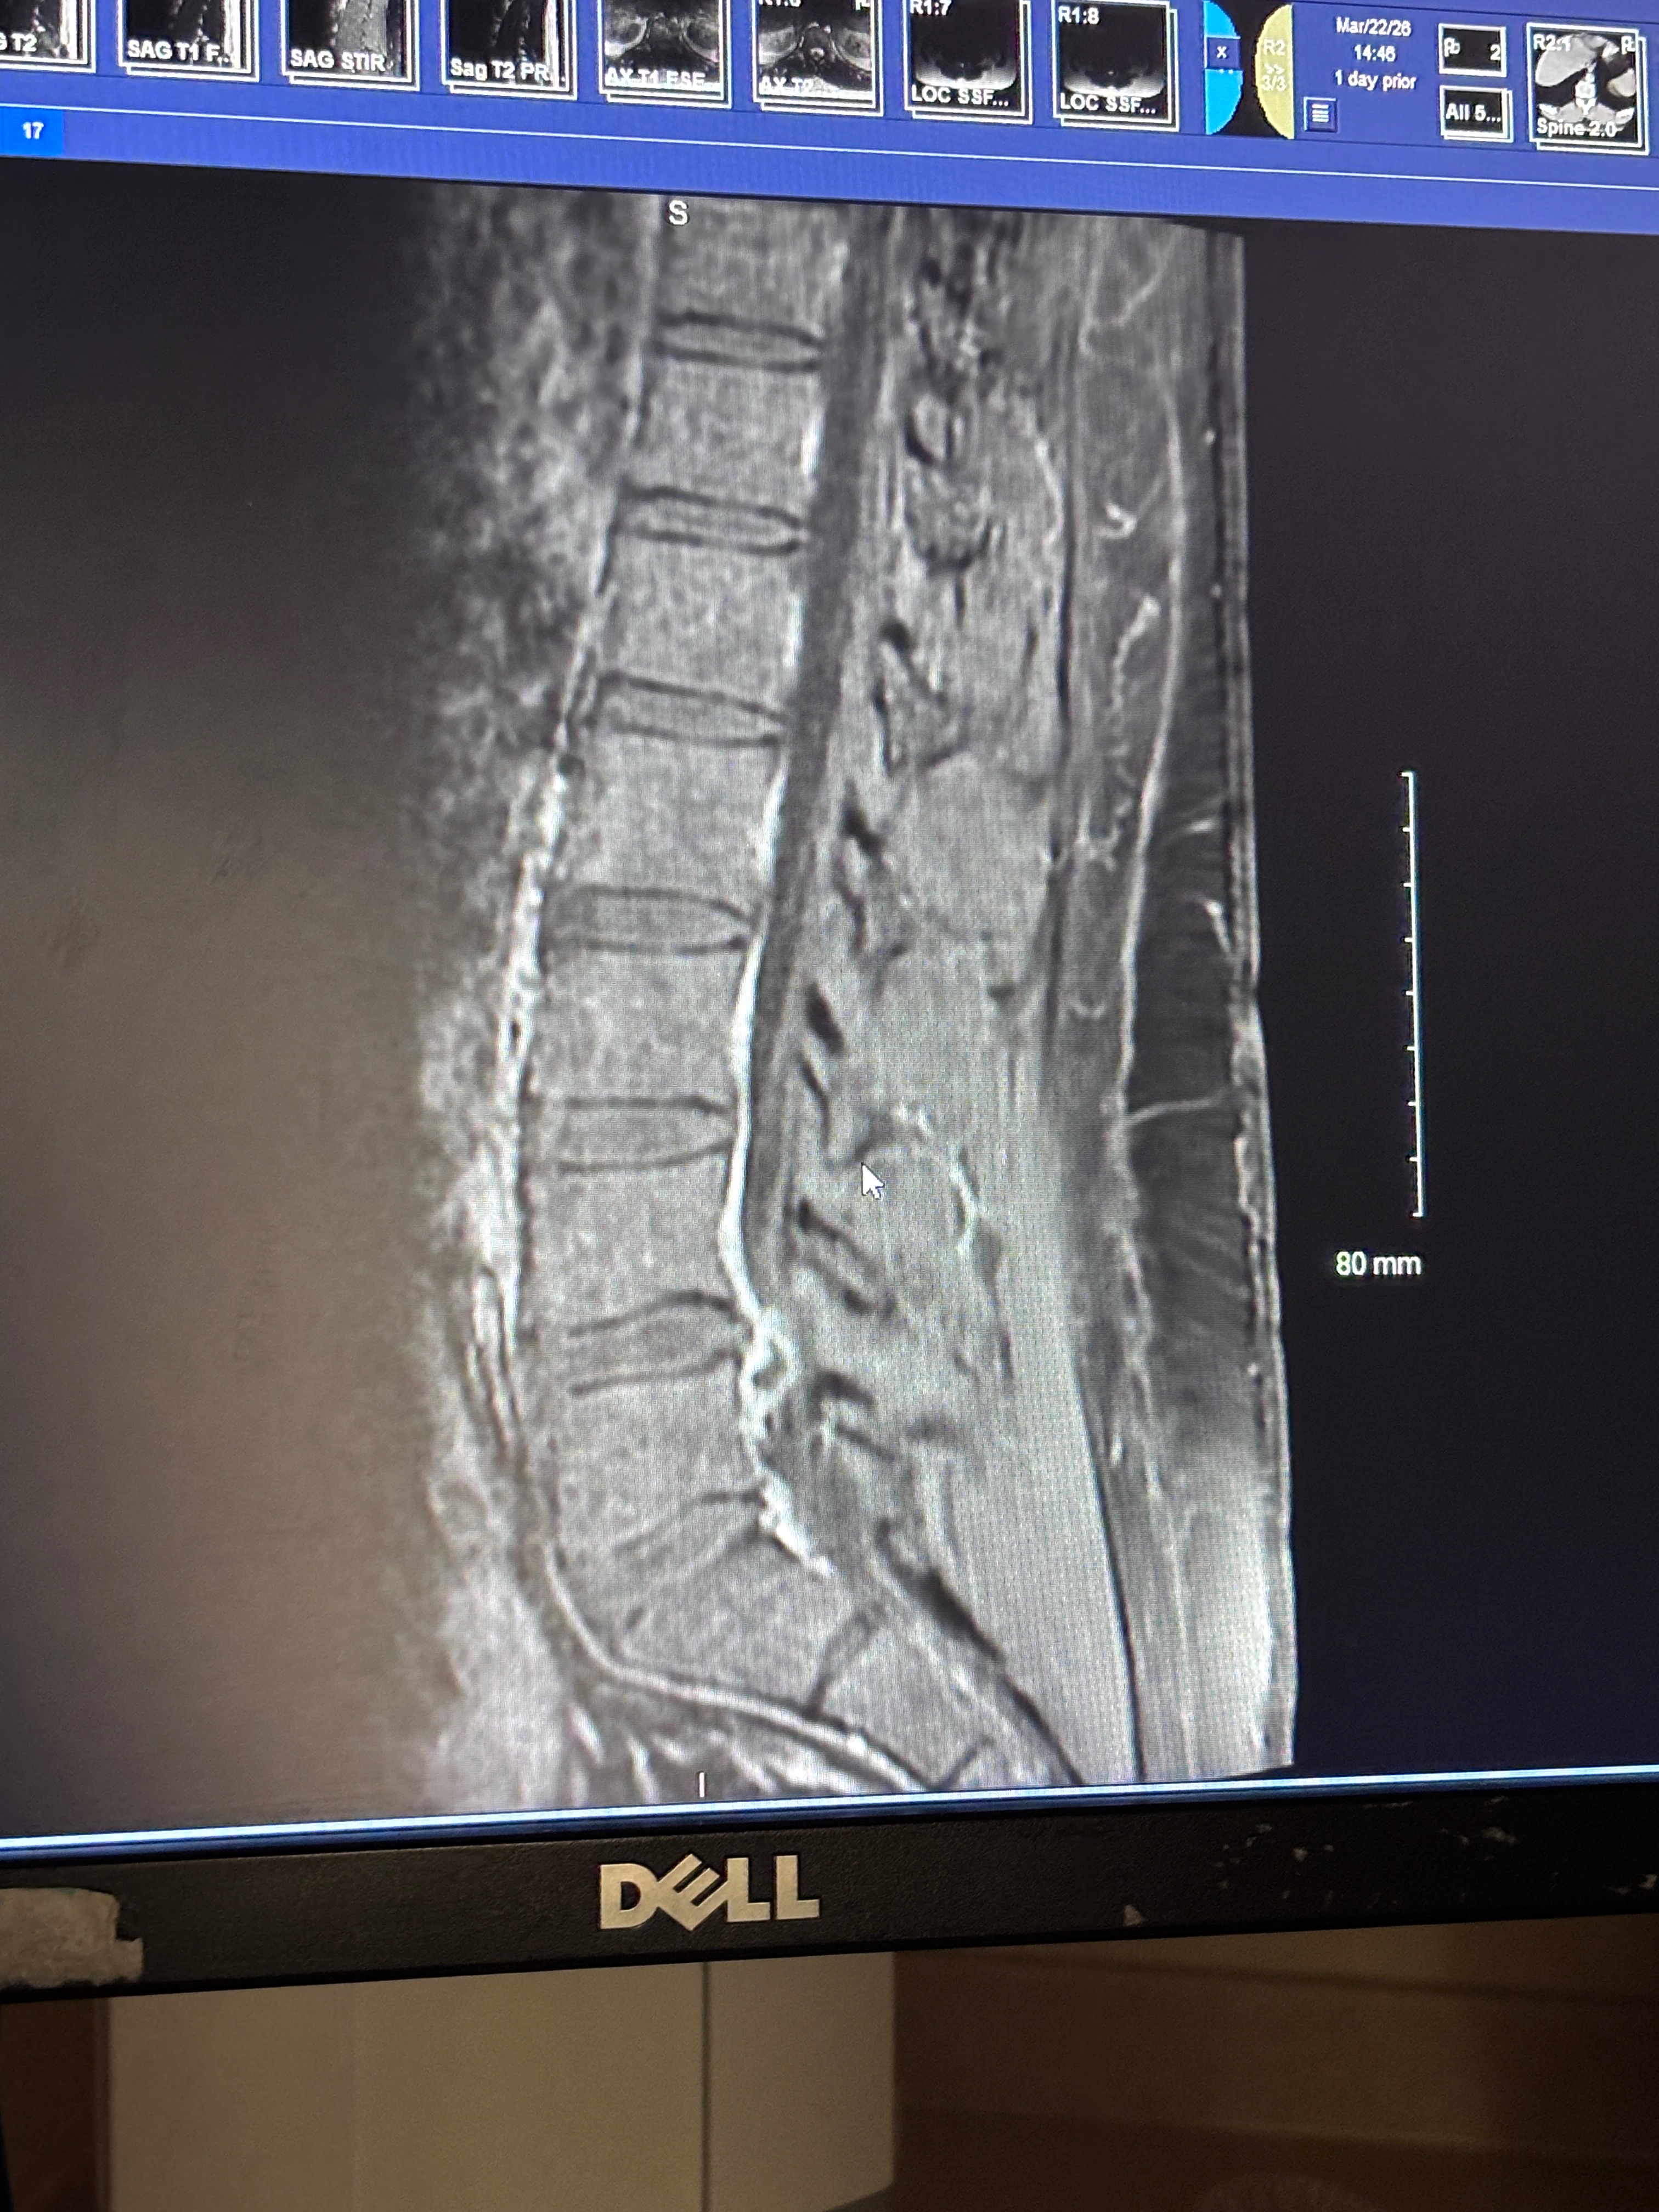

Kyle recently underwent an L4-5 spinal fusion and is now facing a challenging road to recovery. Due to the surgery, he will be out of work for three months, spending this time rehabilitating at home. It’s not easy for him to be away from his job, but his health and healing must come first. During this period, Kyle will be receiving in-home care from family members and friends, as we do everything we can to support his recovery and help him regain his strength.